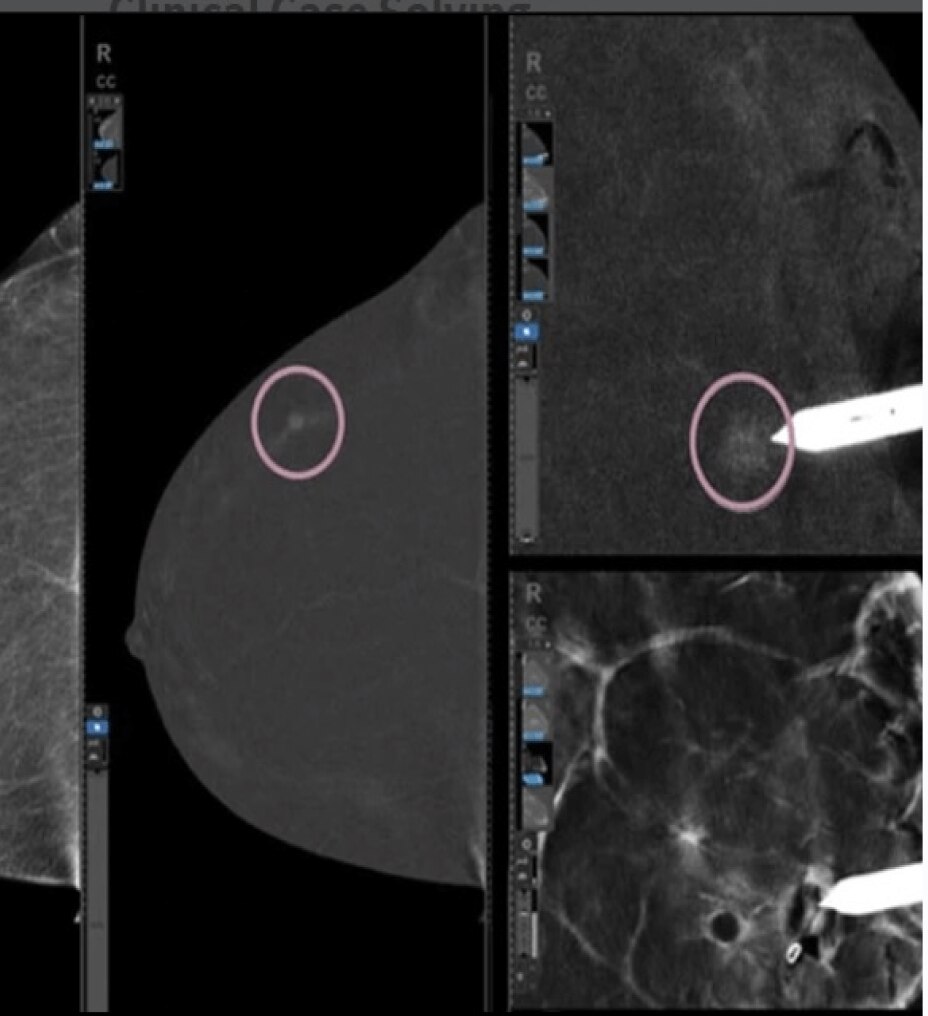

マンモグラフィ